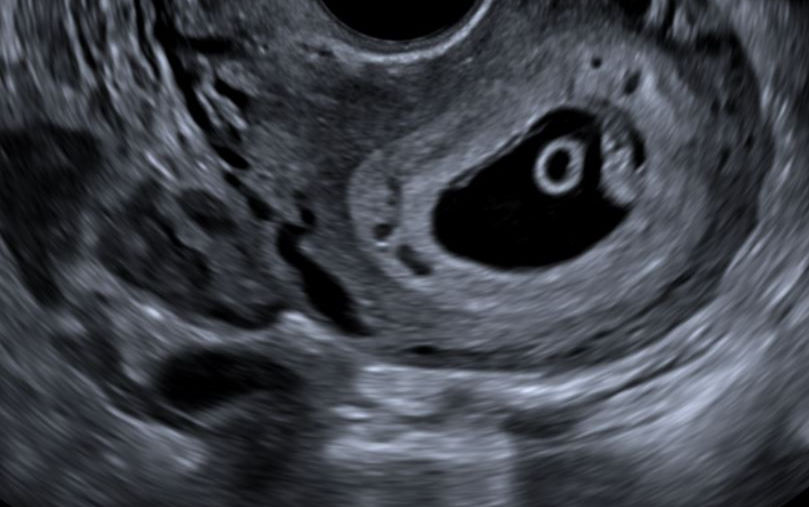

El examen de ecografía obstétrica inicial en Quito, realizada entre la semana 5 y 10 de embarazo (vía Transvaginal), es un momento crucial y emocionante. Esta ecografía temprana permite confirmar la presencia del embrión, verificar su vitalidad detectando el latido cardíaco, determinar la edad gestacional con gran precisión, y evaluar si el embarazo es intrauterino o extrauterino. Es una primera "mirada" a tu futuro bebé.